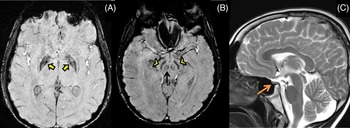

Her routine blood investigations were normal except for hyperglycemia. Electrocardiogram and echocardiography were within normal limits. Pure tone audiometry showed bilateral mild sensorineural hearing loss. Magnetic resonance imaging (MRI) brain showed mineralization in bilateral globus pallidus interna, substantia nigra, and red nucleus on susceptibility-weighted images (SWI) (Figure 1A and B) along with bilateral frontoparietal discrete white matter hyperintensities on T2-weighted images(Figure 1C) and partial empty sella with small-sized hypophysis (Figure 1D). Serum estradiol level of 23.2 pg/mL (normal range in premenopausal females being 30–400 pg/mL) and progesterone levels of 0.04 ng/mL (normal range being 0.1–0.7 ng/mL in the follicular stage and 2–25 ng/mL in the luteal stage) were low, whereas serum follicular stimulating hormone (FSH) level of 33 IU/L(normal range 3–10 ), luteinizing hormone (LH) level of 27.4 IU/L (normal range 2–8 ) were high suggesting a hypergonadotropic hypogonadism secondary to ovarian failure. Ultrasound pelvis showed a small infantile uterus with ill-defined ovaries.

Figure 1: Magnetic resonance imaging (MRI) of the brain shows mineralization in bilateral globus pallidus interna (yellow arrows), substantia nigra (yellow arrowheads), and red nucleus (black arrow) on susceptibility-weighted images (A and B) along with bilateral frontoparietal white matter hyperintensities on T2-weighted images (C) and partial empty sella with small sized hypophysis (D-orange arrow).